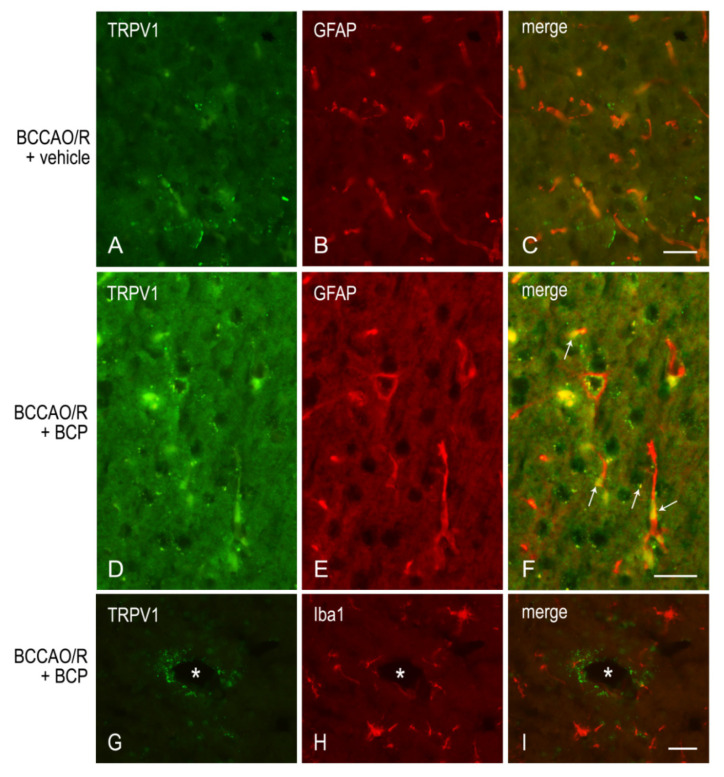

To draw a parallel of the molecular changes observed by Western blot analysis with the tissue morphology, we performed immunostainings of the rat brain sections with the same antibodies used for Western Blot analysis. Immunoreactivities for all examined markers were localized to neuronal structures distributed throughout the rostro-caudal extension of the brain (Figure 3, Figure 4, Figure 5 and Figure 6). As regards the frontal cortex, TRPV1-LI appeared as sparse dot-like elements and tiny varicose nerve fibers distributed mostly close to blood vessels or around them (Figure 3 and Figure 6A,D,G). Neuronal perikarya showing a faint intracytoplasmic staining with a dust-like aspect were further detectable (Figure 6A,D). Labeling of the meningeal lining of the cortex was also detectable. By contrast with the scarcity of TRPV1-LI, the BDNF- and trkB-like immunoreactive structures were numerous and identifiable as neuronal perikarya and proximal processes and nerve fibers distributed throughout the cortical layers, having the aspect of loose networks of thin filaments and punctate elements in the superficial layers, and straight neuronal processes with a prevalent radial orientation in the deep layers (Figure 4 and Figure 5). Double labeling for either TRPV1 and GFAP (astrocyte marker) or TRPV1 and Iba1 (microglia marker), carried out by means of indirect immunofluorescence in selected series of brain sections from BCCAO/R rats showed that, in both BCP- and vehicle-treated rats, rare TRPV1-labelled nerve fibers and dot-like elements were also GFAP-immunoreactive (Figure 6C,F), whereas TRPV1/Iba1 colocalization was virtually absent (Figure 6B).

3.2. TRPV1-like Immunoreactive Structures in BCCAO/R with and without BCP

Similar to available studies on the distribution of TRPV1-LI in the rodent CNS [ref. 49,ref. 50], our results show that TRPV1 occurs in the frontal cortex where it localizes to cell bodies, mainly with an intracytoplasmic distribution, and dot- and thread-like elements suggestive of nerve fibers. However, at variance with previous studies [ref. 49,ref. 50], in our hands, the cortical TRPV1-labeling was light (under baseline and BCP-treated BCCAO/R conditions) to virtually absent (in BCCAO/R condition after vehicle-treatment) and, when present, the TRPV1-positive structures often underlined the course of some blood vessels in the cortex. It remains to clarify whether the vessel-associated immunoreactive elements we observed are genuine nerve fibers, as suggested by their varicose appearance, or stand for non-nervous vascular elements as shown by transmission electron microscopy (TEM) in the rat brain [ref. 49]. TRPV1 mRNA has also been reported in several other vascular beds in the rat [ref. 76,ref. 78]. Interestingly, the TRPV1 on sensory nerve terminals mediates local vasodilation, while the vascular TRPV1 leads to vasoconstriction [ref. 76]. Cavanaugh and coll [ref. 76] suggested that, in thermoregulatory tissues, activation of TRPV1 on vascular smooth muscle cells could counteract nerve-related changes in vascular tone in response to physiological TRPV1 agonists. Provided that a diverging role for TRPV1 was also possible in the brain vessels, it could be speculated that the TRPV1 increase induced by BCP in BCCAO/R compared to sham rats is partly involved in controlling the homeostasis of the cortical vascular bed under the reperfusion challenge.

This last inferring is further supported by our findings that after the BCP-treatment, beyond the TRPV1 increase, significant GFAP downregulation and partial TRPV1-/GFAP-like immunoreactivity colocalization were detectable in the BCCAO/R compared to the vehicle-treated rats. While the evaluation of GFAP expression in our setting warrants further investigations to clarify the astroglial involvement in the regulation of TRPV1 relative levels in the brain after BCCAO/R, it is tempting to hypothesize that the TRPV1-bearing astrocytes may be contributing to the regulation of vascular tone under the hypoperfusion/reperfusion challenge. Interestingly, TRPV1-positive astrocytes have already been demonstrated in the rat spinal cord [ref. 79] and brain [ref. 49]. As already suggested [ref. 49], astrocytes may represent another critical element by which TRPV1 may intervene to regulate the vascular bed, either by modulating the tone of cerebral vessels or modulating the blood-brain barrier permeability in response to an inflammatory challenge. Indeed, though with a time longer than that of our BCCAO/R model, it has been shown that the inflammatory milieu generated by 2.5 h of ischemic brain injury stimulated a strong astroglial response. This response was featured by cell hypertrophy and hyperplasia [ref. 77,ref. 80], and it was suggested that it may lead to an increased expression of GFAP, partly because the number of GFAP-positive astrocytes increases [ref. 81].

Concerning the microglial marker Iba1, the significant general effect of the BCCAO/R main factor evidenced by the ANOVA analysis was not paralleled by statistically significant post-hoc differences in Iba1 relative levels between sham and BCCAO/R rats, with or without BCP. The TRPV1/Iba1 double immunolabeling argues against the possibility of a microglial expression of the receptor, and no patent changes in the morphology of Iba1-positive elements could be either observed. The fact that, in our hands, no patent histological damage, as to induce evident microglia activation, could be detected in the rat brain after BCCAO/R is difficult to interpret. Numerous previous literature data report heavy microglial activation in the acute phase of an ischemic stroke in several experimental protocols [ref. 82], the shortest survival time possibly being that of 20 min after forebrain ischemia of 25 min [ref. 83]. However, more recent findings showed that some microglial cells were activated within 10 min following BCCAO and reached a strong reaction within 20 min without reperfusion [ref. 84] and refs therein. Interestingly, it has also been shown that the extent of microglial reaction not only does not increase with the extension of the survival time after BCCAO, serving possibly as a neuroprotectant during the vessel occlusion, but can easily be reversed by reperfusion [ref. 84]. This suggests the possibility that in our setting we are merely underestimating the microglia changes or searching too late for them to be appreciable.